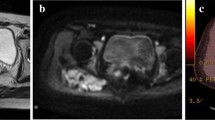

Figure 3 shows an example of the relationship between the signal and DF growth behavior.

a, b An 18-year-old female with a DF to the posterior compartment of the left knee (white stars). a Axial T2-weighted fat-saturated MR image showing a DF with a T2 ratio < 1. b T2-weighted fat-saturated axial MR image of the same patient, 80 months later, showing stable lesion volume and signal. c, d A 62-year-old male with a DF to the medial part of the left knee (white arrows). c Coronal T2-weighted fat-saturated MR image showing a DF with a T2 ratio > 1. d Coronal T2-weighted fat-saturated MR image of the same patient 17 months later showing an increase in lesion volume and signal